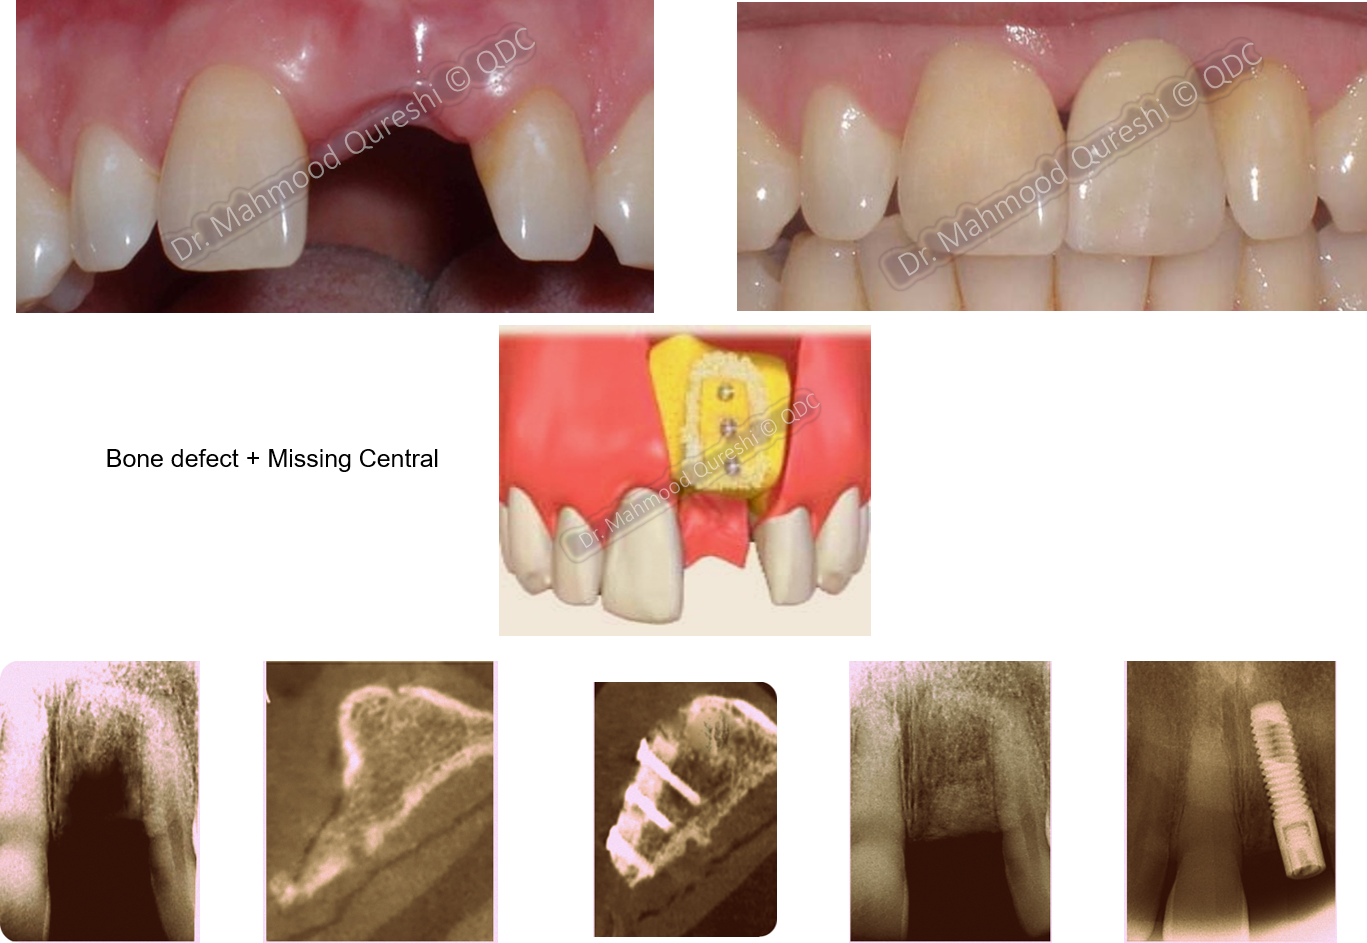

BONE GRAFTING

Bone Grafting/Augmentation is aimed at

Restoring, Recreating, or Enhancing BONE VOLUME FOR STABLE, LONG-LASTING RESULTS.

• Rebuilds lost bone to provide a strong foundation for dental implants.

• Addresses bone deficiencies caused by:

• Tooth loss over prolonged periods.

• Injuries or trauma to the jawbone.

• Periodontal disease, resulting in bone loss.

Dental Bone Grafting: A Scaffold for Regeneration

• Purpose: Acts as a framework to encourage natural bone growth and repair.

Dr. MQ’s Approach to Bone Grafting

• Utilizes cutting-edge techniques, including autografts for the most natural results.

• Carefully places the graft in deficient areas to stimulate regeneration and achieve optimal aesthetics and functionality.